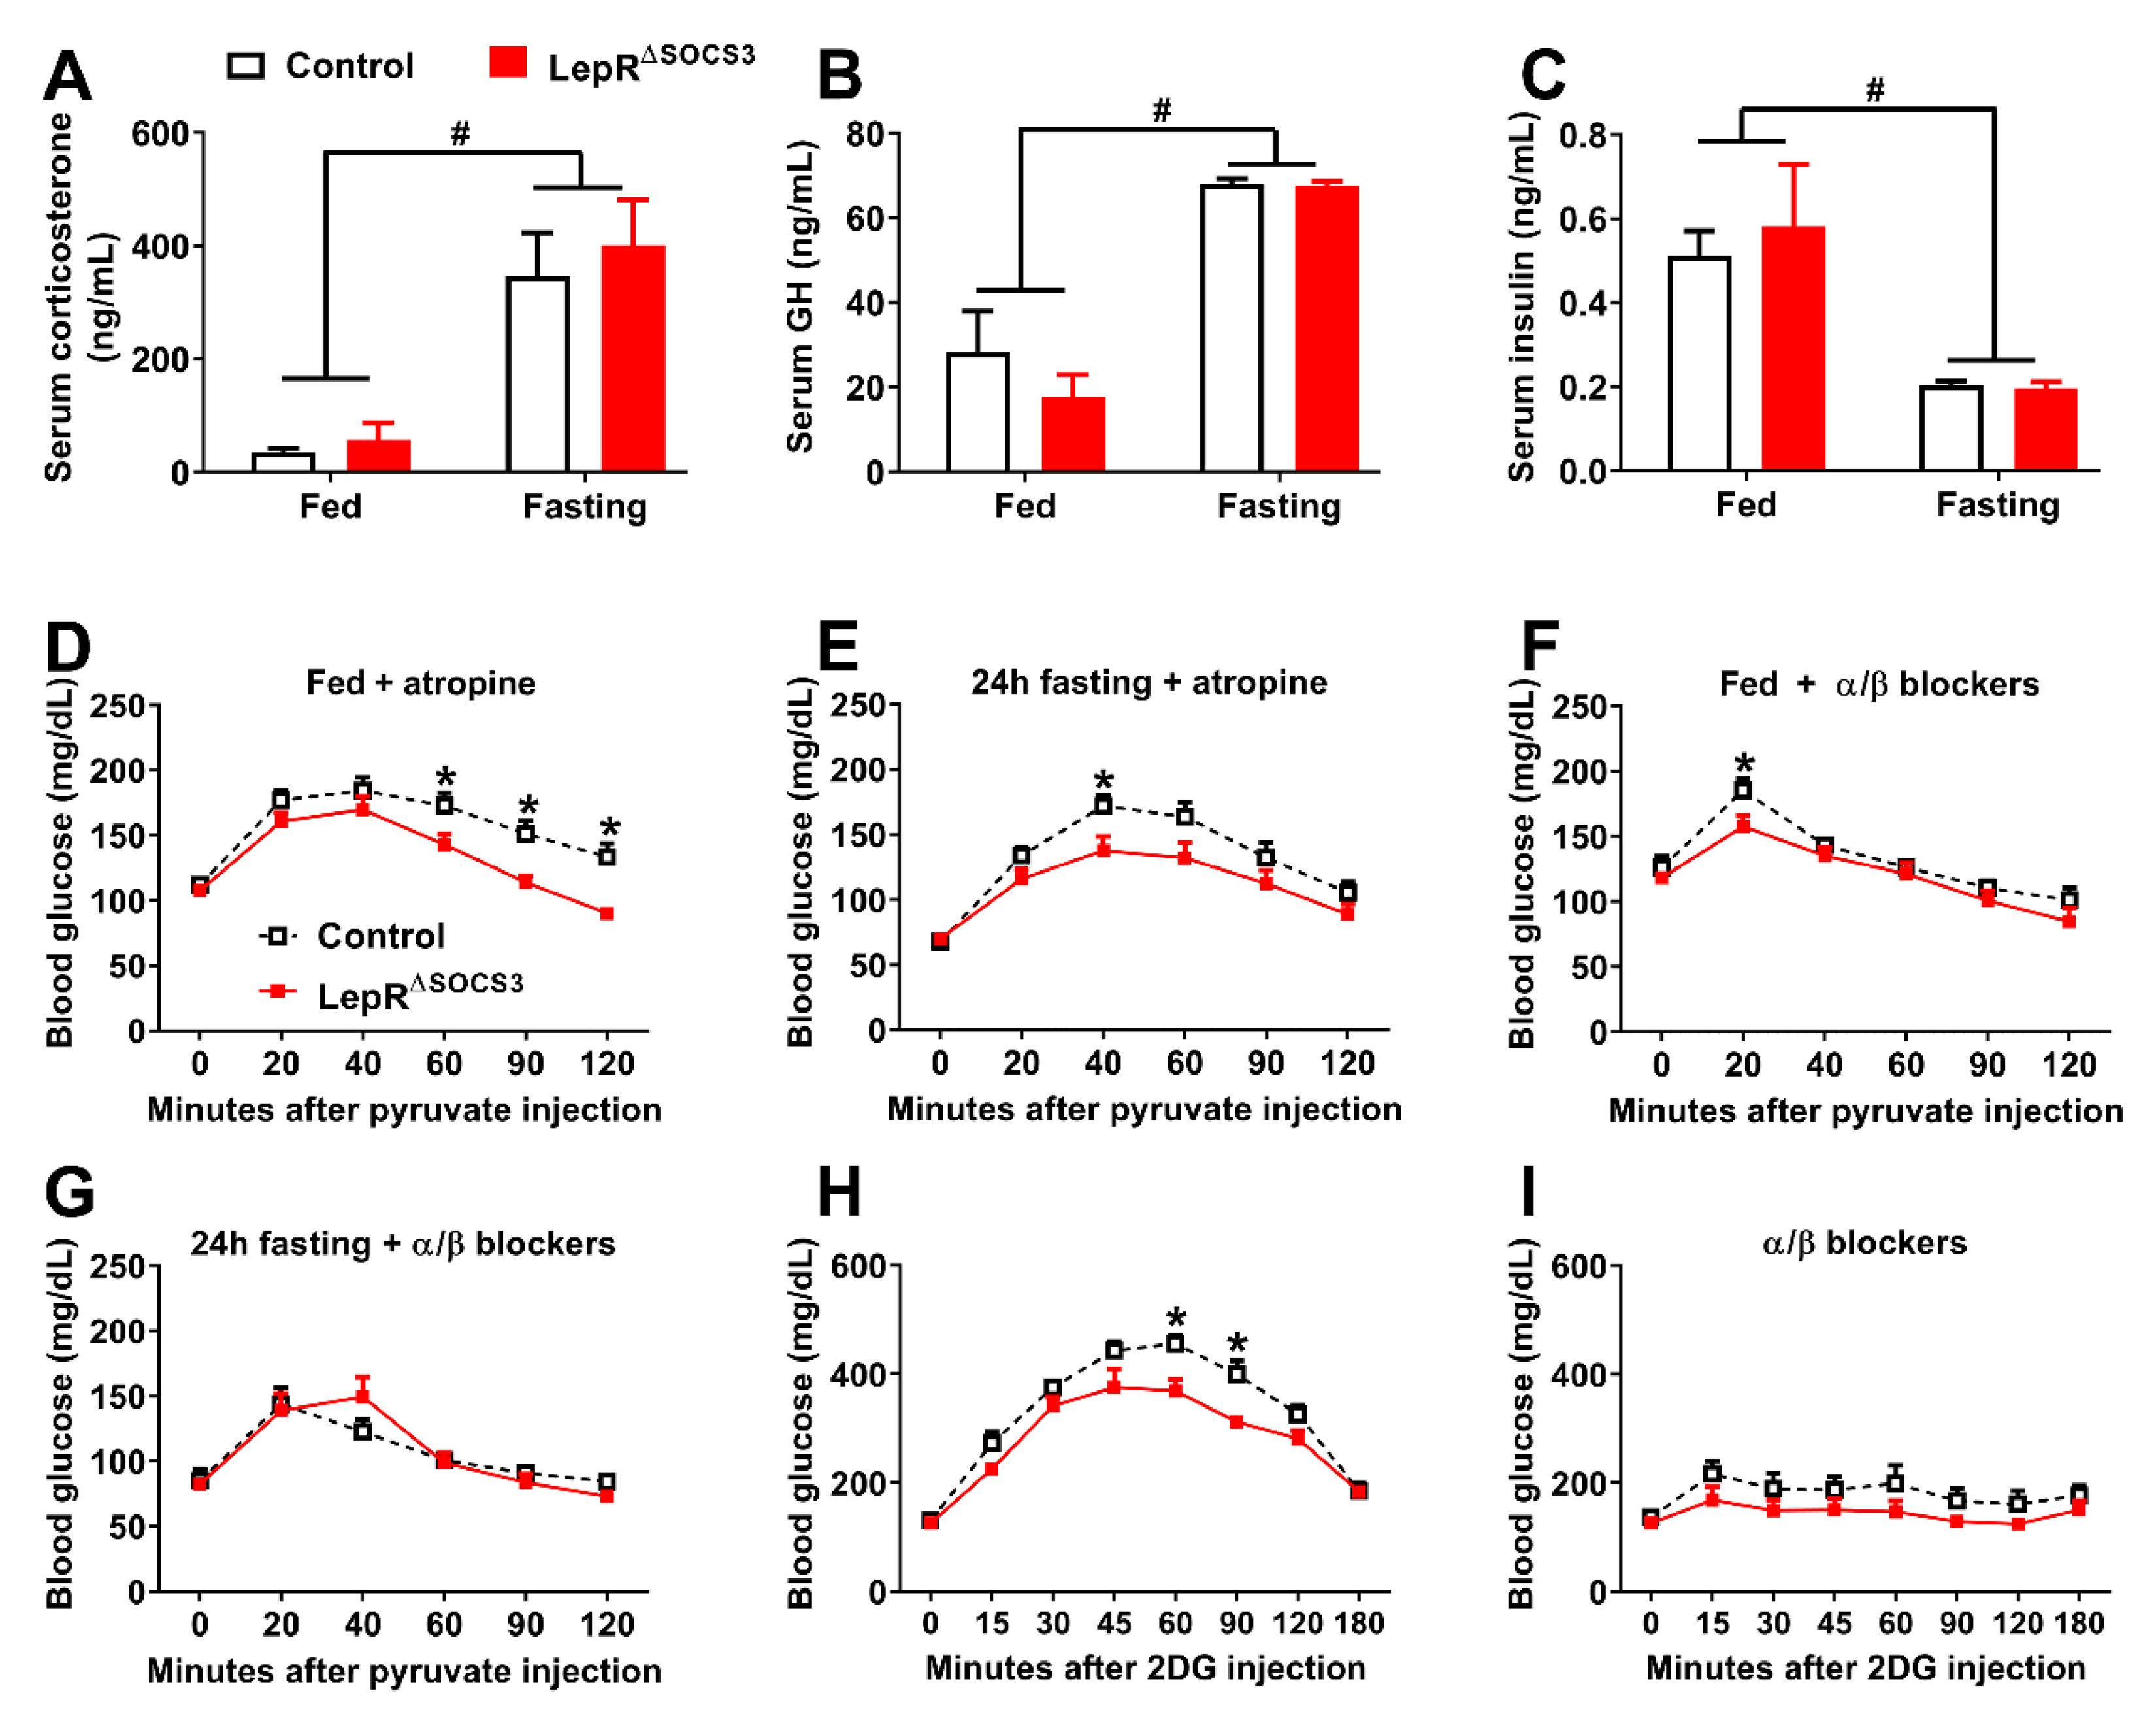

2.4. LepR∆SOCS3 Mice Exhibit Fasting-Induced Hypoglycemia That Is Associated with Reduced Gluconeogenesis

2.5. Possible Alterations in the Sympathetic Nervous System Explain the Impaired Gluconeogenesis and Counterregulatory Response of LepR∆SOCS3 Mice